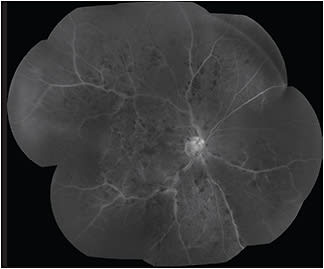

FA is the gold standard for visualizing retinal vasculature in vivo. It enables the identification of microaneurysms, macular edema and neovascularization. It can also be used to monitor the size of the foveal avascular zone. FA guides therapy by identifying the source of fluorescein leakage for possible focal laser treatment and monitoring response to panretinal photocoagulation. FA is most helpful to evaluate the extent and severity of retinopathy, particularly the degree of peripheral ischemia via standard FA and, most recently, via ultra-widefield FA (UWFA) (Figure 2). UWFA can detect predominantly peripheral lesions not visible on standard FA that are associated with an increased risk of DR.4 UWFA allows for identification of peripheral neovascularization and peripheral retinal ischemia, thus identifying patients who would benefit from panretinal laser photocoagulation and/or anti-vascular endothelial growth factor (VEGF) therapy or patients at increased risk of neovascularization/vitreous hemorrhage who would benefit from more frequent follow up.6 However, widespread use of UWFA is limited by the cost of the technology.